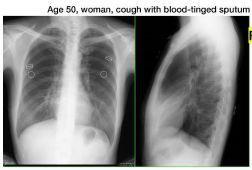

1.